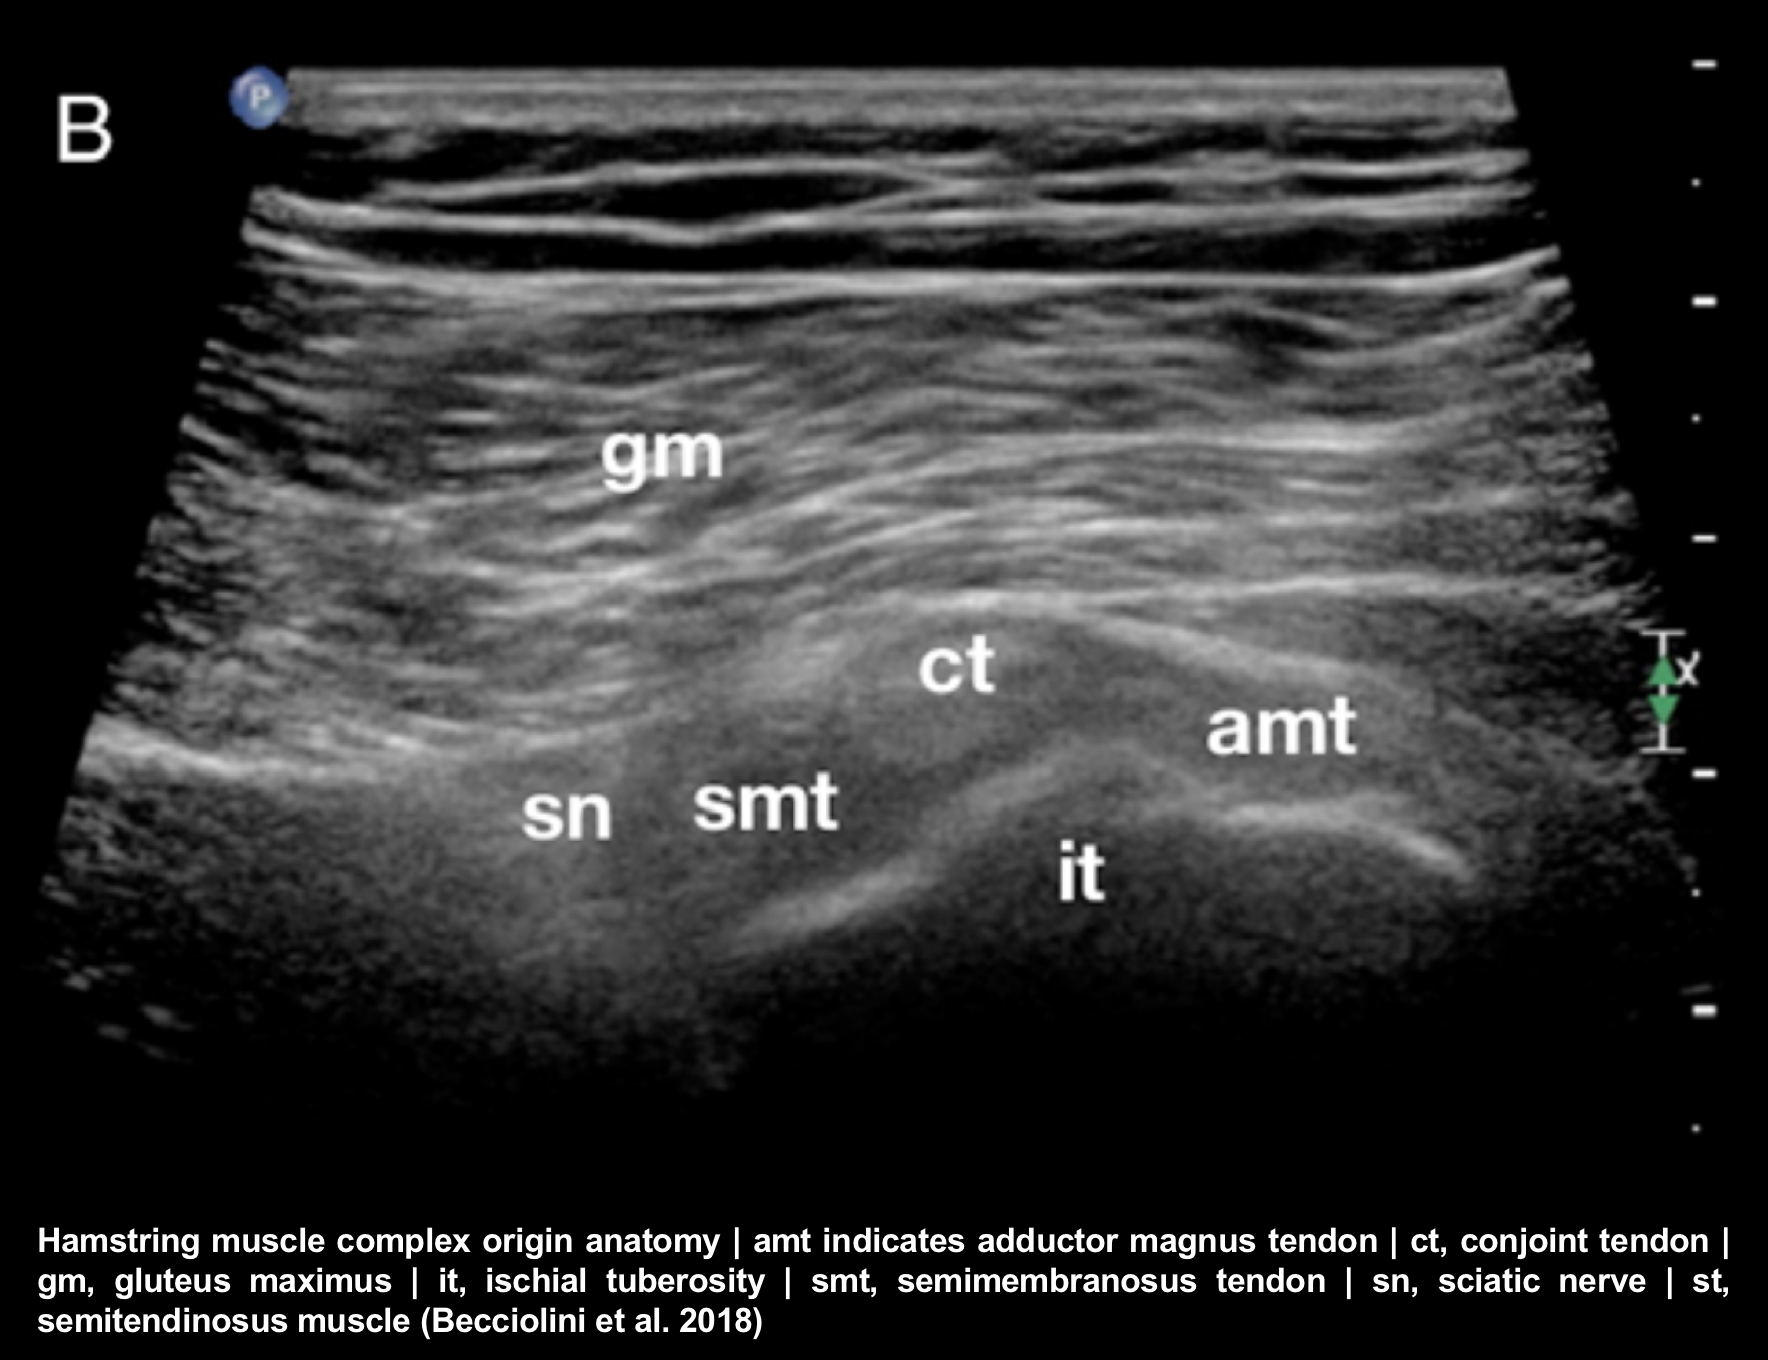

Proximal Hamstring Injury Robert Howells Hamstring Muscles The hamstring muscles are three large muscles that run down the back of the thigh and help control the hips and knees. Learn about the best hamstring exercises for working all your hamstring muscles, and maximize your hamstring muscle growth. The hamstring muscles flex the knee joint and extend the thigh backward to propel movement. Hamstrings consist of 3 muscles;. Hamstring Muscles.